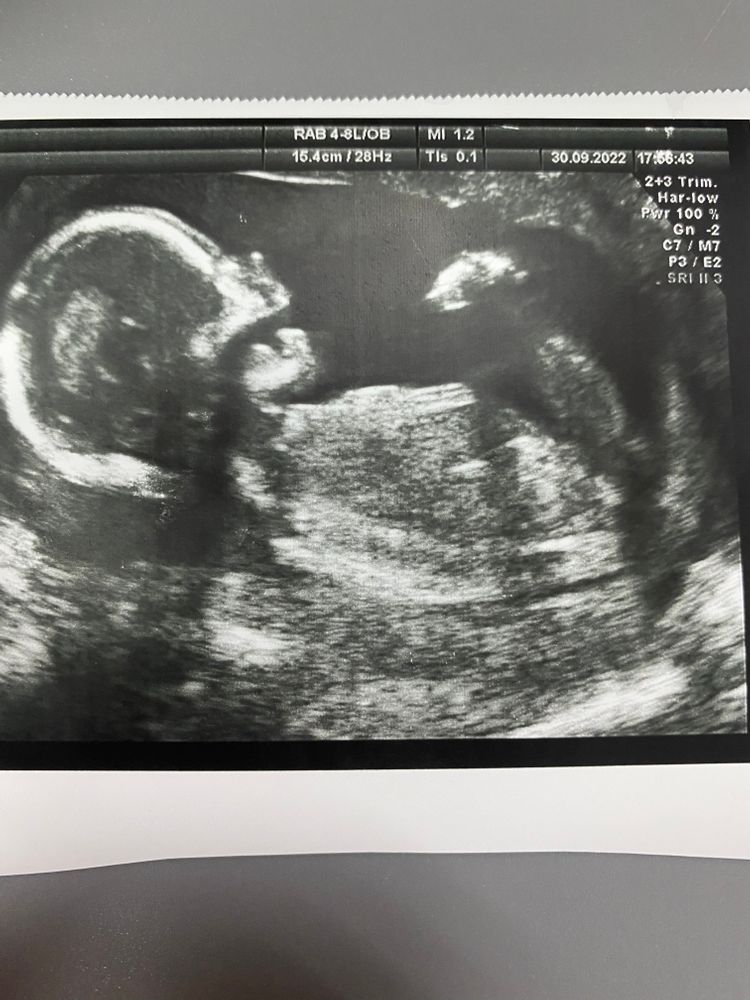

Точно девочка?)))

По такому снимку, к сожалению, достоверно не определить)) Понимаю Ваше нетерпение... Но... дождитесь второго скрининга. Там сомнений уже не будет. А пока наслаждайтесь беременностью и ожиданием здорового малыша)

Похоже на девочку) половой бугорок под "девчачьим" углом)

И мне так кажется. У сильно ажурные косточки, мальчики грубее